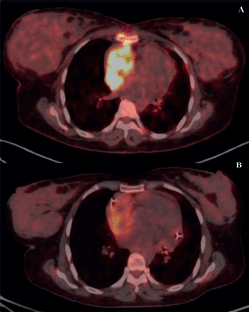

Figure 4. PET scans of a patient with locally advanced/unresectable cardiac angiosarcoma (a): Before chemotherapy and (b): After 5 cycles of single-agent gemcitabine.

Of 9 evaluable responses (both as first line and subsequent lines) among palliative setting 5 (55.5%) were PR (Figures 3c and 4), 3 (33.3%) were SD and 1 (11.2%) progression. Median progression-free survival (PFS) with systemic therapy was 5.4 months (95% CI: 0–13.7) (Figure 5a). Median overall survival (OS) was 1.2 months (those who did not receive systemic therapy) versus 19.2 months (those who received systemic therapy) (95% CI: 0–42.2) (Figure 5b). The median OS for the entire cohort was 5.1 months (95% CI: 0.2–10.0) (Figure 5c).